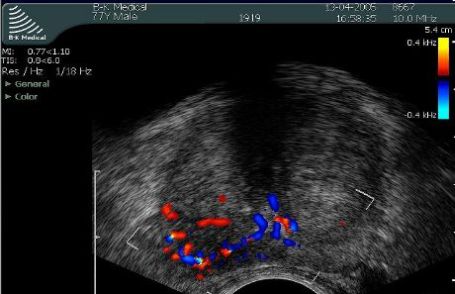

Widok gruczołu krokowego w przekroju poprzecznym podczas TRUS

Poprzeczny przekrój gruczołu krokowego widziany podczas TRUS z Dopplerem